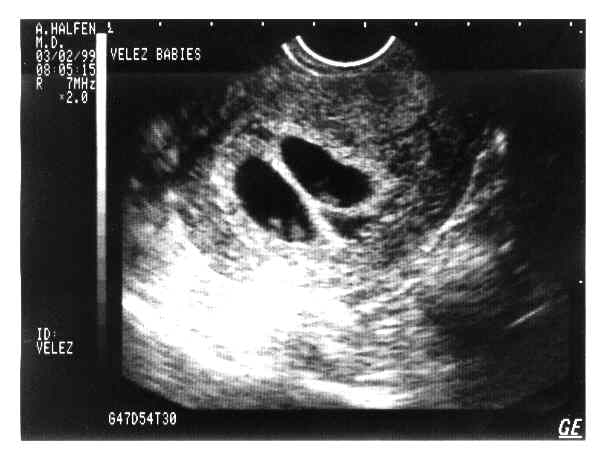

V-Twins

eggs2.JPG - 19.8 K eggs3.JPG - 22.4 K eggs4.JPG - 11.7 K babies-1a.JPG - 21.3 K